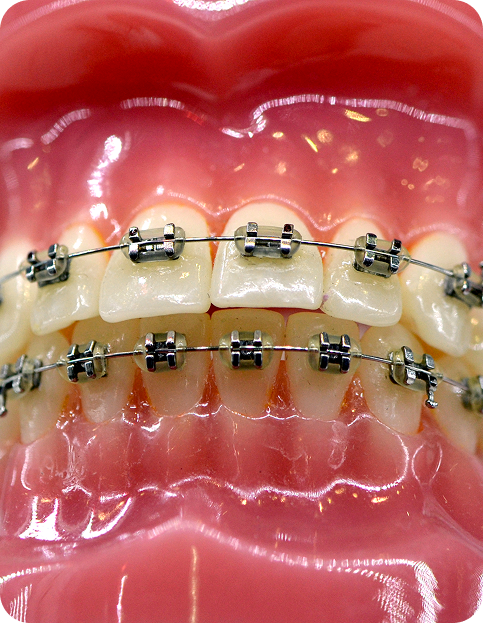

These are the braces, which are stuck onto the teeth with the help of chemicals. Broadly speaking, they are made up of steel or tooth-coloured ceramic. With the help of wire elastics, e-chains the teeth are pushed back. You might experience some discomfort and pain after the braces are placed. But with painkillers and time, patients get used to it. Fixed braces are used in cases where irregularity of teeth or malocclusion is more. Proper care should be taken in terms of brushing & cleaning of teeth regularly.

steel braces

The most common and recognizable braces are the stainless steel braces. These braces are very durable and different color ties may be used with them for decorative purposes to enhance the orthodontic experience.